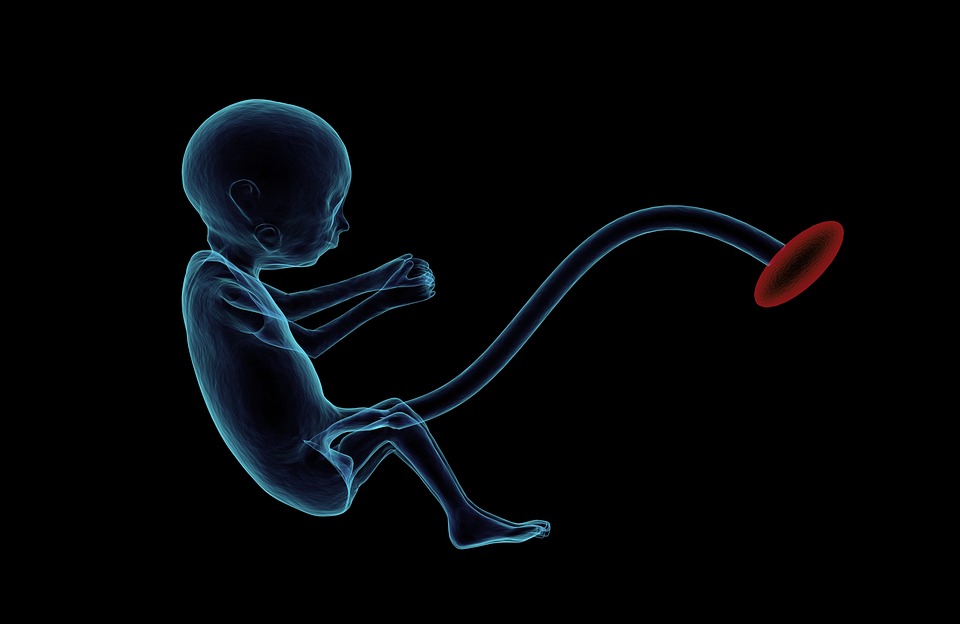

Ćelije kože će se razviti u jajnu ćeliju, tvoreći sa spermatozoidima embrion koji će se usađivati u matericu. Taj proces, in vitro gametogenesis - IVG, dosad je isproban samo na miševima

U roku od deceniju ili dve, kažu istraživači, naučnici će po svoj prilici moći da bebu stvore od ćelija ljudske kože koje će se razviti u jajnu ćeliju, tvoreći sa spermatozoidima embrion koji će se usađivati u matericu. Taj proces, in vitro gametogenesis - IVG, dosad je isproban samo na miševima. Ali biolozi za matične ćelije kažu da je samo pitanje vremena kada će se taj postupak koristiti u ljudskoj reprodukciji - i otvoriti zapanjujuće mogućnosti.

IVG podrazumeva slojeve kompleksnog bioinženjeringa. Naučnici prvo moraju da uzmu ćelije kože odraslog čoveka - mogle bi to da budu i druge, ali kožne je najlakše uzeti - i reprogramiraju ih da rade kao embrionske matične ćelije koje mogu da se razviju u nekoliko različitih vrsta ćelija, a da onda istim faktorima koji prirodno to čine, navedu matične ćelije da postanu jajne ili spermatozoidi.

Istraživači u Japanu, predvođeni Kacuhikom Hajašijem, prošle godine ovim metodom stvorili su održiva jajašca od ćelija kože odraslog ženskog miša, i proizveli embrione koji su usađeni u mišicu koja je kasnije rodila zdrave mladunce.